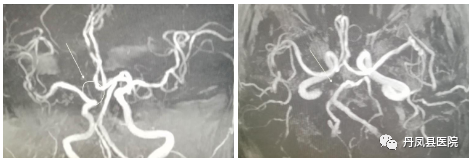

![颅脑血管3.png]()

颅脑血管MRA

颅脑血管MRA,是一种无创伤性血管成像技术,无需注射造影剂,能在短时间内获得清晰的脑血管图像。